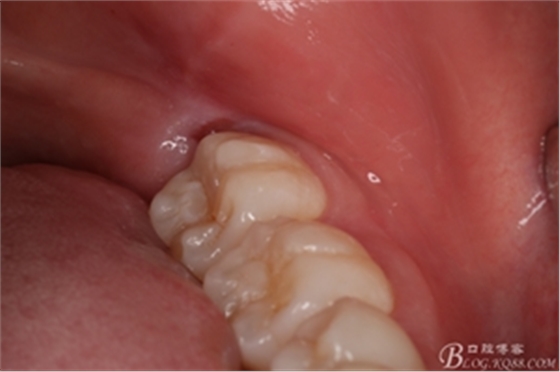

圖1.術(shù)前的口內(nèi)照片:38未萌出、牙齦輕度紅腫,37遠(yuǎn)中有盲袋。